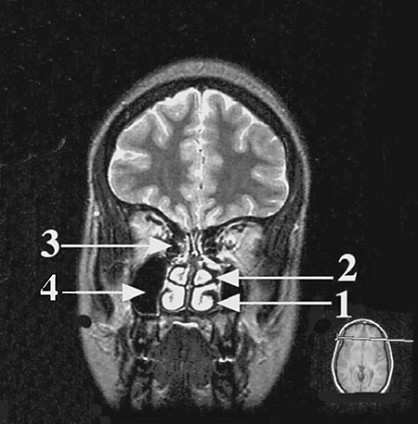

In the coronal section of the head shown in following figure arrow 2 points to a structure that belongs to which of the following?

Arrow 2 points to the middle nasal concha, which is part of the ethmoid bone. Arrow 3 points to the ethmoid sinus, which also belongs to the ethmoid bone. The inferior nasal concha (arrow 1) is a separate bone (choice B). The maxillary bone (choice C) is located more laterally and does not contribute to the nasal conchae. The maxillary sinus, a part of the maxillary bone, is indicated by arrow 4. The vomer bone (choice E) forms part of the nasal septum (choice D), which can be seen here as the thin line between the nasal conchae. The nasal conchae have no attachment to the septum.